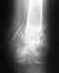

Находилась на стационарном лечении с 26 января по 14 февраля в отделении неврологии. С 15 февраля на амбулаторном лечении. Принимаю фенотропил 1 т. утром, курантил по2 т. 3 раза в день. Состояние нестабильное, с периодическими ухудшениями: беспокоят головокружения, головная боль, тошнота по утрам, общая слабость, слабость в правых конечностях, по утрам онемение правой руки. периодически повышается артериальное давление. 21 марта прошла К.Т. в г. Уфе (высылаю). Консультирована нейрохирургом, неврологом в РКБ - диагноз: ЗЧМТ, ушиб головного мозга с легким правосторонним гемипарезом, вестибулопатией, данных за хроническую внутричерепную гематому нет.В последние 10 дней состояние заметно ухудшилось. Усилилась общая головная боль, боль в затылочной области, усилилось головокружение, беспокоит пульсирующий шум в голове, тремор конечностей.Вопрос: Могу ли я пройти у вас консультацию и, если необходимо, лечение?